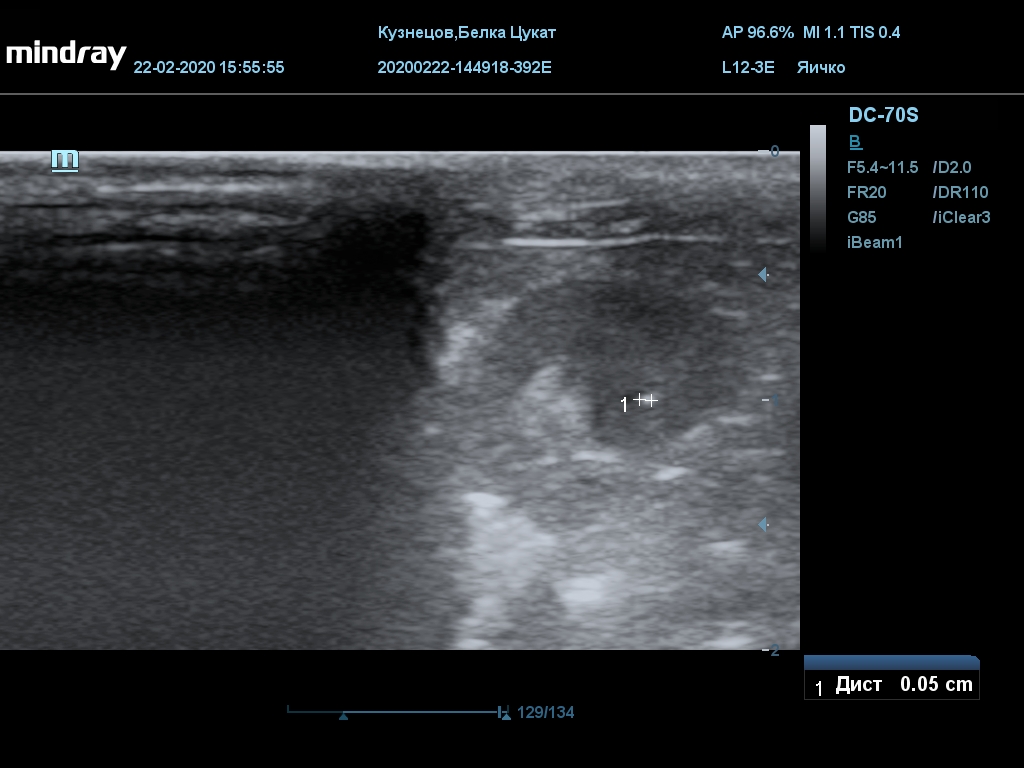

УЗИ

(почки, мочевой пузырь и, предположительно, простата)

Обращаю внимание, что делала УЗИ и писала заключение узист, которая специализируется на кошках и собаках, поэтому она сделала узи и описала, как смогла, но тонкостей грызунячьей анатомии она не знает.

Приложил только фото, есть ещё пара видео, но не знаю, как тут выложить, и надо ли.

Мочевой пузырь объём 12,1 х 7,6 х 11 мм. Стенка не утолщена, 0,5 мм, содержимое не однородное, до половины объёма гипоэхогенная мелкодисперсная взвесь. Макс. размер включений 0,8 мм. Теней нет.

Заключение: УЗпризнаки уролитиаза, объёмная структура каудальнее мочевого пузыря. Признаки расширения левой лоханки.

УЗИ

(почки, мочевой пузырь и, предположительно, простата)

Обращаю внимание, что делала УЗИ и писала заключение узист, которая специализируется на кошках и собаках, поэтому она сделала узи и описала, как смогла, но тонкостей грызунячьей анатомии она не знает.

Мочевой пузырь объём 12,1 х 7,6 х 11 мм. Стенка не утолщена, 0,5 мм, содержимое не однородное, до половины объёма гипоэхогенная мелкодисперсная взвесь. Макс. размер включений 0,8 мм. Теней нет.

Заключение: УЗпризнаки уролитиаза, объёмная структура каудальнее мочевого пузыря. Признаки расширения левой лоханки.